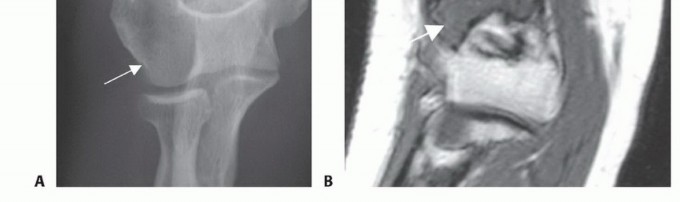

التصوير التشخيصي

تلعب تقنيات التصوير دورًا حاسمًا في تشخيص أورام العضد البعيد وتحديد مدى انتشارها.

الأشعة السينية العادية

- الغرض: هي الخطوة الأولى لتحديد موقع الورم في العظم، وتقدير حجمه الأولي، وتكوين تشخيص تفريقي.

- ما تظهره: يمكن أن تكشف عن التغيرات في بنية العظم، مثل التدمير العظمي، أو تكوين عظم جديد غير طبيعي (التكلس)، أو الكسور المرضية. بعد العلاج الكيميائي، يمكن استخدامها لتقييم استجابة الورم للعلاج.

الرنين المغناطيسي

- الغرض: هو الأكثر دقة لتحديد مدى انتشار الورم داخل وخارج العظم (intra- and extraosseous extent)، وكذلك للكشف عن النقائل القافزة (skip metastases).

- ما يظهره: يوفر صورًا مفصلة للأنسجة الرخوة، مما يساعد في تقييم قرب الورم من الأوعية الدموية الرئيسية (الشريان العضدي) والأعصاب (المتوسط، الزندي، الكعبري). يعتبر حاسمًا للتخطيط الجراحي وتحديد طول الجزء العظمي الذي سيتم استئصاله.

- مراجعة شاملة لدراسات التصوير: يتم تقييم صور الرنين المغناطيسي (T1-weighted MRI) للذراع بالكامل لتحديد مدى انتشار الورم داخل العظم وتحديد مستوى القطع العظمي لضمان هامش آمن (عادة 2-3 سم من العظم السليم). كما يتم مراجعة صور الأشعة المقطعية والرنين المغناطيسي لتقييم امتداد الورم في الأنسجة الرخوة وقربه من الهياكل العصبية الوعائية.